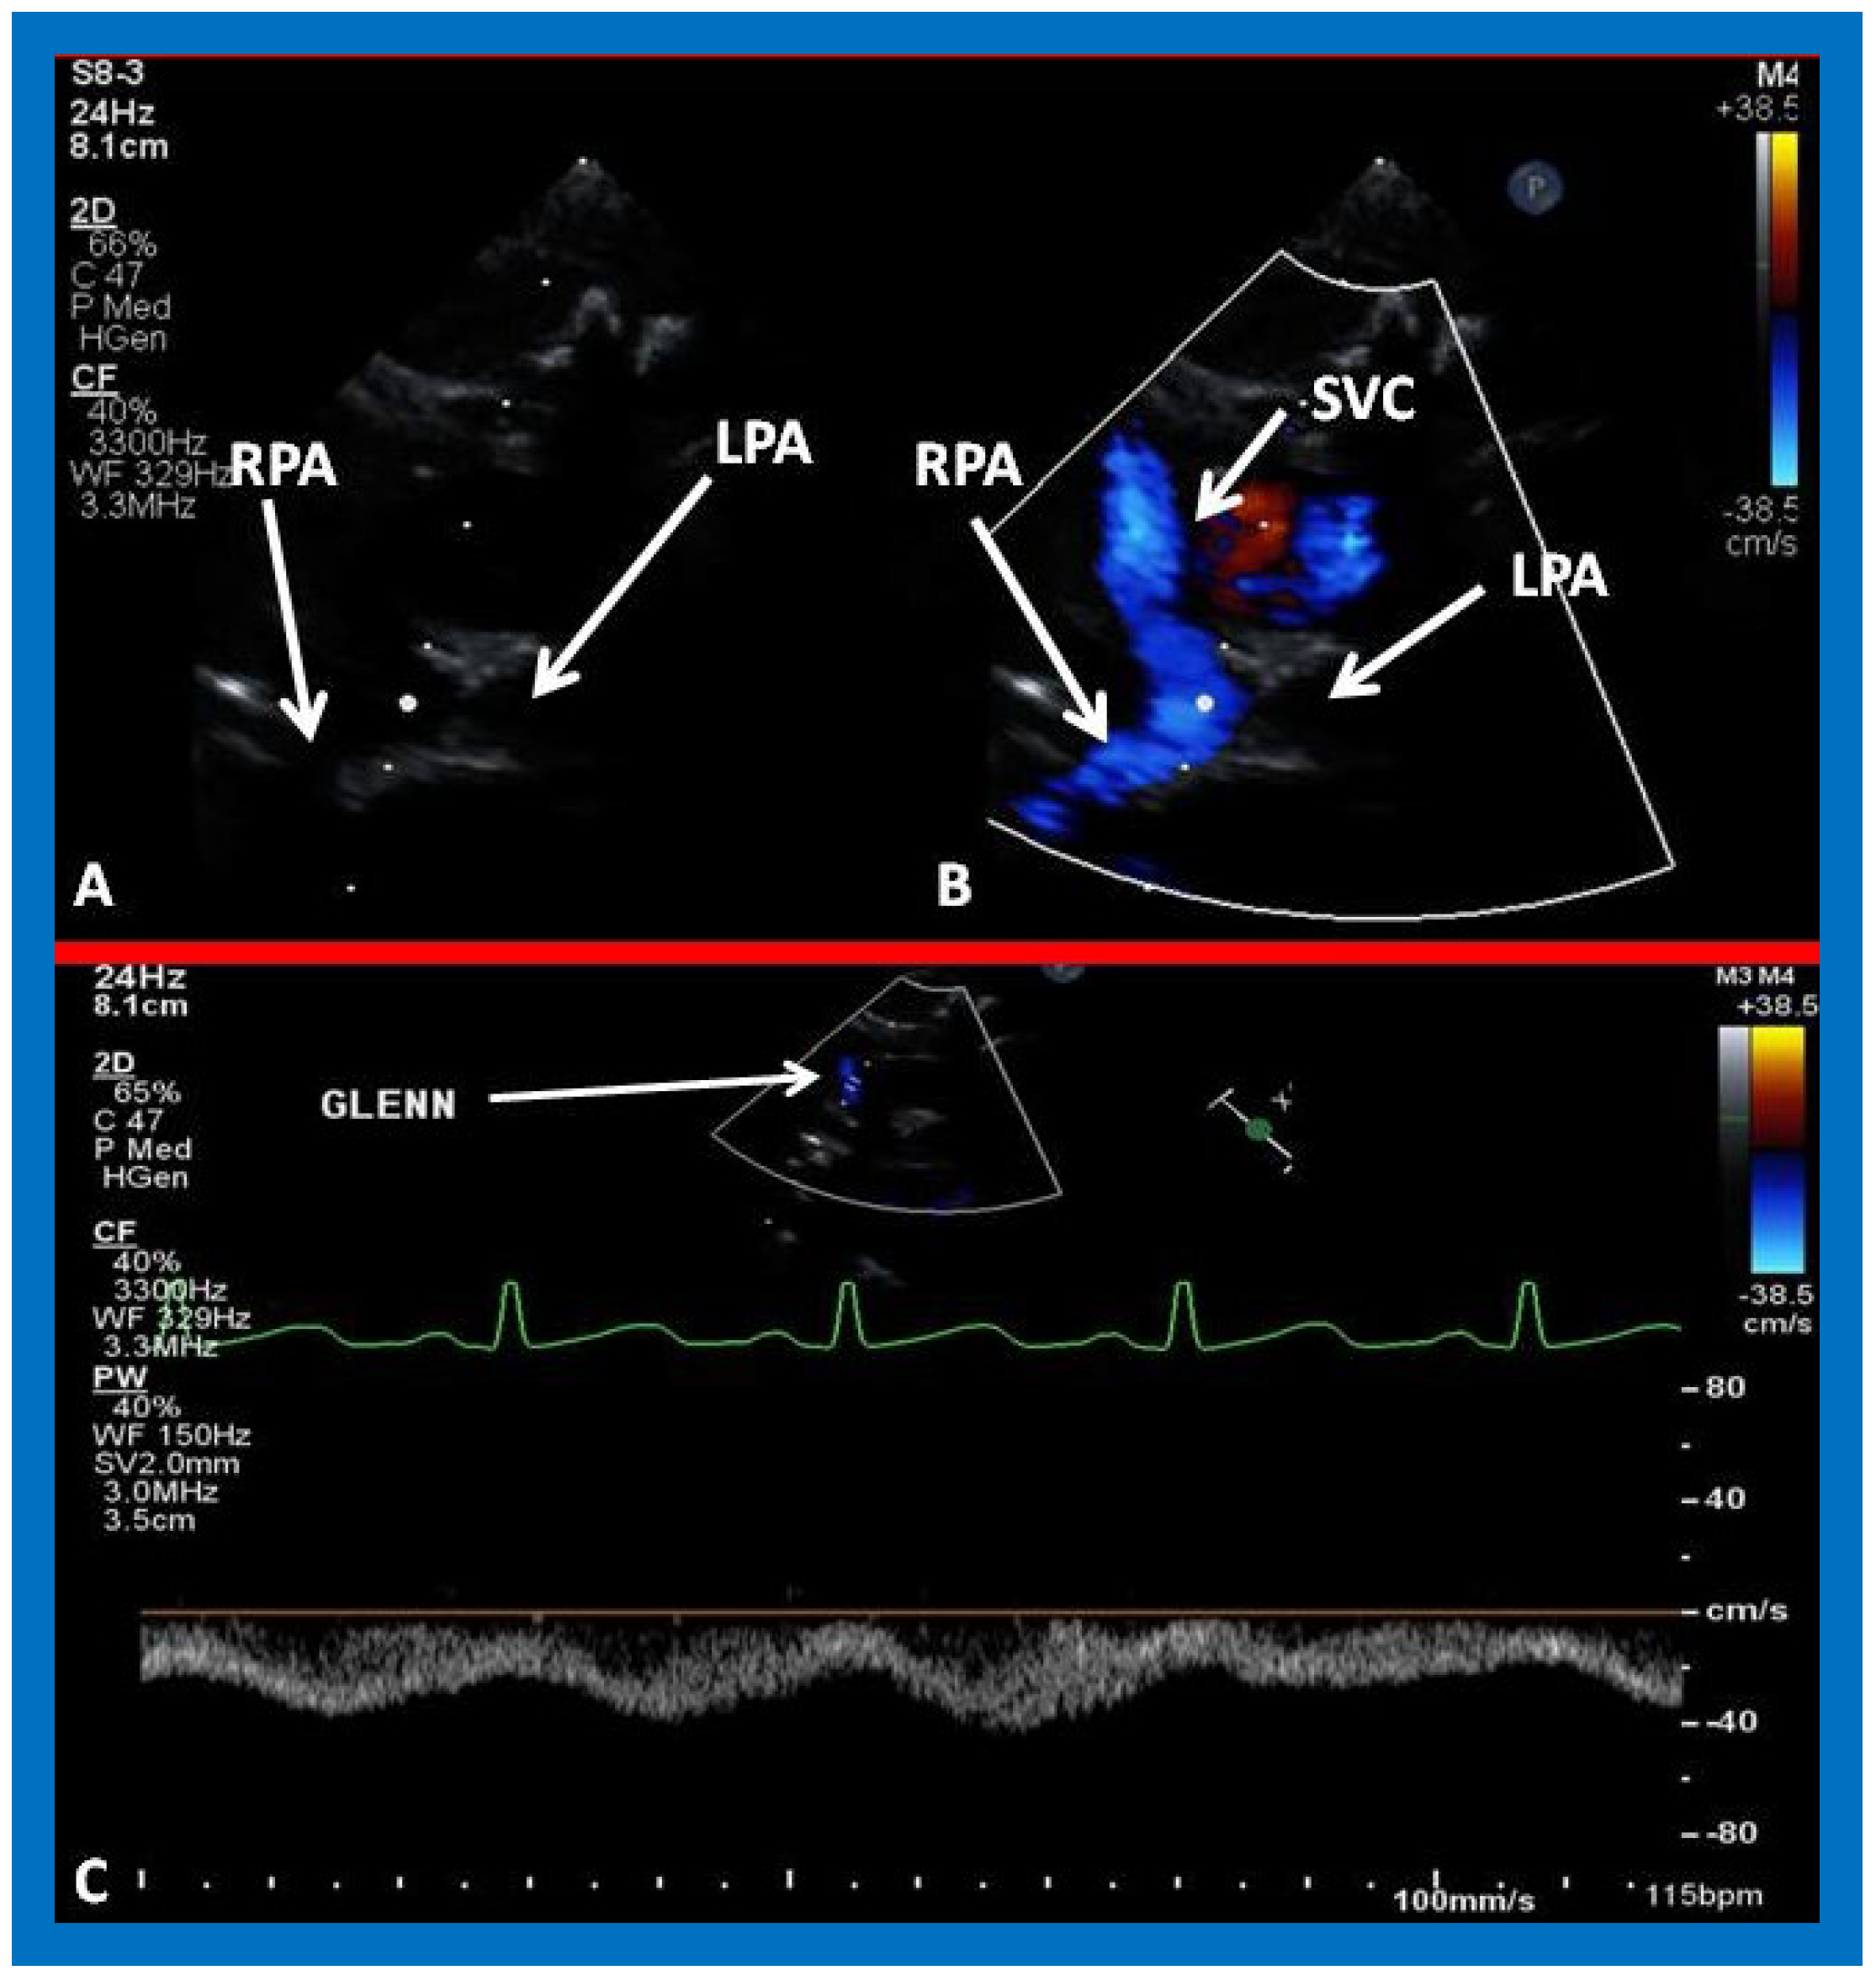

Figure 25. Selected video frames from suprasternal notch view demonstrating bidirectional Glenn shunt; the superior vena cava (SVC) is shown emptying into the right (RPA) and left (LPA) pulmonary arteries by color flow imaging (A). Low Doppler flow velocity across the shunt (B) indicates unobstructed Glenn.

Figure 26. (A,B) Selected video frames from suprasternal notch view demonstrating bidirectional Glenn shunt. In (A), the right (RPA) and left (LPA) pulmonary arteries are shown by 2D. The superior vena cava (SVC) was not clearly seen. In (B), the SVC is shown emptying into the RPA by color Doppler (B). The LPA did not show color flow because it was in a different plane of imaging than RPA, but is seen by 2D (B). (C) Low Doppler flow velocity across the Glenn shunt indicates unobstructed flow.

5.3. Echocardiographic Evaluation Following Bidirectional Glenn

Following bidirectional Glenn, the LV size is likely to decrease (normalize) and LV should maintain normal systolic function. This is because of decreased LV volume overload following bidirectional Glenn and the removal of aorto–pulmonary shunt. The 2D imaging of the bidirectional Glenn is difficult to accomplish, but color flow imaging (Figure 25A, Figure 26B, and Figure 27B) from a suprasternal notch or high parasternal views will help image the bidirectional Glenn. Low pulsed Doppler velocity across the superior vena cava (SVC)–PA junction (Figure 25B and Figure 26C) would indicate no obstruction. Turbulent and high velocity Doppler flow suggests the obstruction of the bidirectional Glenn shunt. The size of the branch PAs may be assessed with a combination of 2D and color flow imaging (Figure 26, Figure 27 and Figure 28).